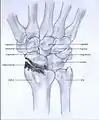

Stages

Post-traumatic osteoarthritis can be classified into four stages.[1][7] These stages are similar between SLAC and SNAC wrists. Each stage has a different treatment.

- Stage I: the osteoarthritis is only localized in the distal scaphoid and radial styloid.

- Stage II: the osteoarthritis is localized in the entire radioscaphoid joint.

- Stage III: the osteoarthritis is localized in the entire radioscaphoid joint with involvement of the capitolunate joint.

- Stage IV: the osteoarthritis is located in the entire radiocarpal joint and in the intercarpal joints. It also may involve the distal radio-ulnar joint (DRUJ).

Stage III

Stage IV